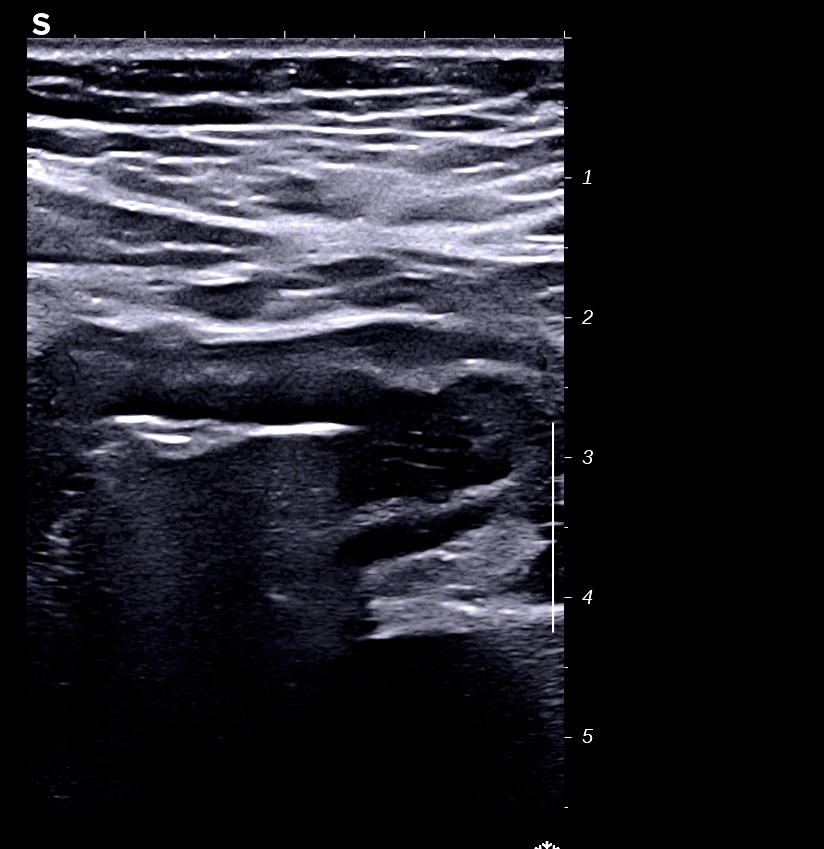

RCH classique, respect de la structure en couche,sous muqueuse très épaissie; musculeuse intacte

Classiquement dans la RCH, l'épaississement concerne les couches 2 et 3, c'est à dire muqueuse (hypoéchogène) et sous muqueuse (hyperéchogène) car il s'agit d'une maladie superficielle de la paroi, la musculeuse (4 ième couche hypoéchogène) est intacte et donc le bord externe est linéaire et régulier

L'épaississement prédomine à la 3 ième couche hyperéchogène (qui fait > 1/3 de la paroi)

Perte des haustrations (le bord externe du colon est rectiligne, lors de la cicatrisation on retrouve des haustrations)

Épaississement continue, circonférentiel, symétrique.